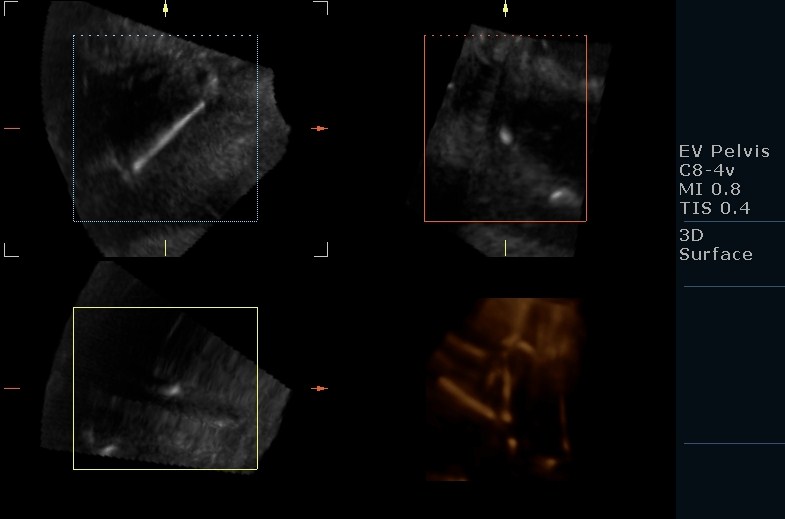

Copper IUD, spotted in Uterus! Copper Iud Questions iud stands for intrauterine device — a birth control method that sits inside your uterus. Freeman says iuds, including the copper iud, are more than 99% effective, making. Paragard also lasts for 10 years. if you’re considering getting a copper iud, you likely have questions. health library / drugs, devices & supplements / paragard® (copper iud) paragard®. Copper Iud Questions.